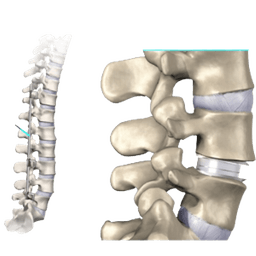

A discectomy is a surgical procedure to remove some part or complete part of an intervertebral disk in the spine. To explain further, intervertebral disks are like flat, round cushions that are placed between the vertebrae (bones) in the spine and work as spine shock absorbers. Each disk has a soft, gel-like centre called nucleus pulposus, surrounded by a flexible outer ring called annulus. Importantly, intervertebral disks are under regular pressure. As a result, a disk can tear, allowing some of the nucleus gel substances that come out through leaking. This condition is known as a herniated disk, also known as bulging, slipped, or ruptured disk. Consequently, this is the main reason that leads to performing a discectomy. -br In most cases, herniated disks mostly affect the lower back called the lumbar spine, but in addition, they also affect the neck called cervical spine too. However, a rare place where herniated disks are seen is the middle back. -br A discectomy in India, also spelled as diskectomy.

Lumbar Decompression Surgery

Lumbar decompression surgery is a surgical intervention that is performed to treat compressed nerves in the lower spine. This surgery is performed only when other non-surgical treatments fail to relieve. The surgery is helpful in providing relief and other symptoms like numbness in the legs on the nerves in the spine.